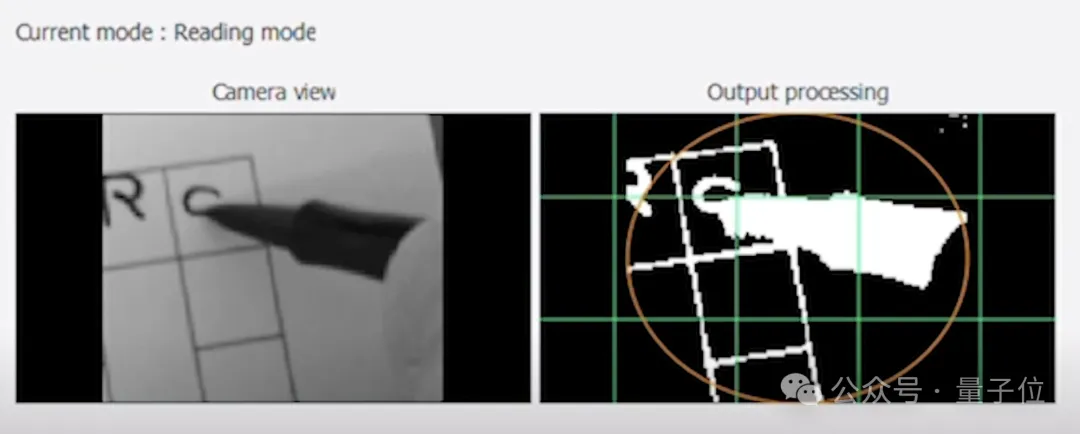

PRIMA的原理是用摄像头捕捉视觉信息,并向芯片发射红外光图案,芯片接收到图案后,将光转换为电信号,并发送到大脑。

不过,PRIMA只是帮助患者在一定程度上重获了阅读文字、分辨人脸等简单视觉能力。

患者看到的图像和正常人仍有区别——由于向芯片发射的是红外光,患者看不到彩色,黑白也和真实世界相反。

但相比于完全看不见,能够阅读文本并分清人脸,已经是很好的结果了。